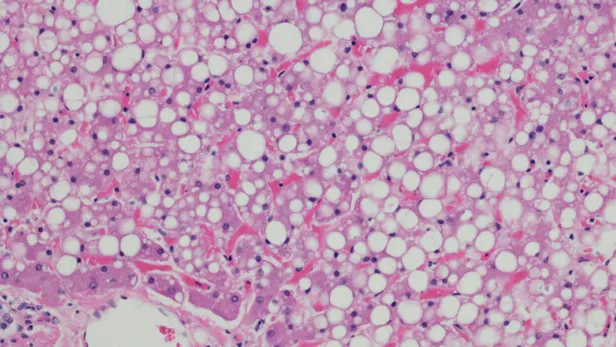

Cardiovascular diseases affect the heart and blood vessels in different ways. For example, blood vessels may become obstructed by fatty deposits, referred to as plaque, leading to heart attacks or strokes.2,4

ATTR-CM is a condition in which a specific protein accumulates in the heart, nerves, and other organs. This accumulation can stiffen the heart walls, hardening the left ventricle of the heart. This is called cardiomyopathy, which can cause heart failure.8